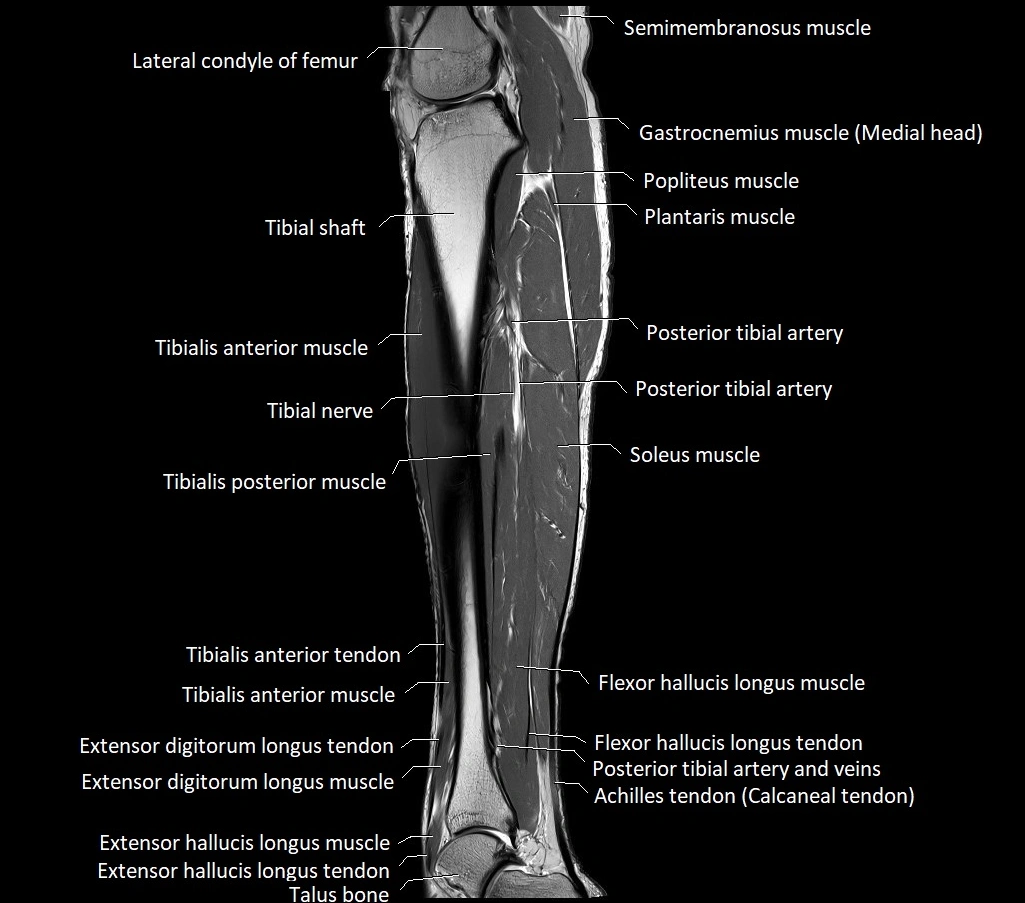

MRI image